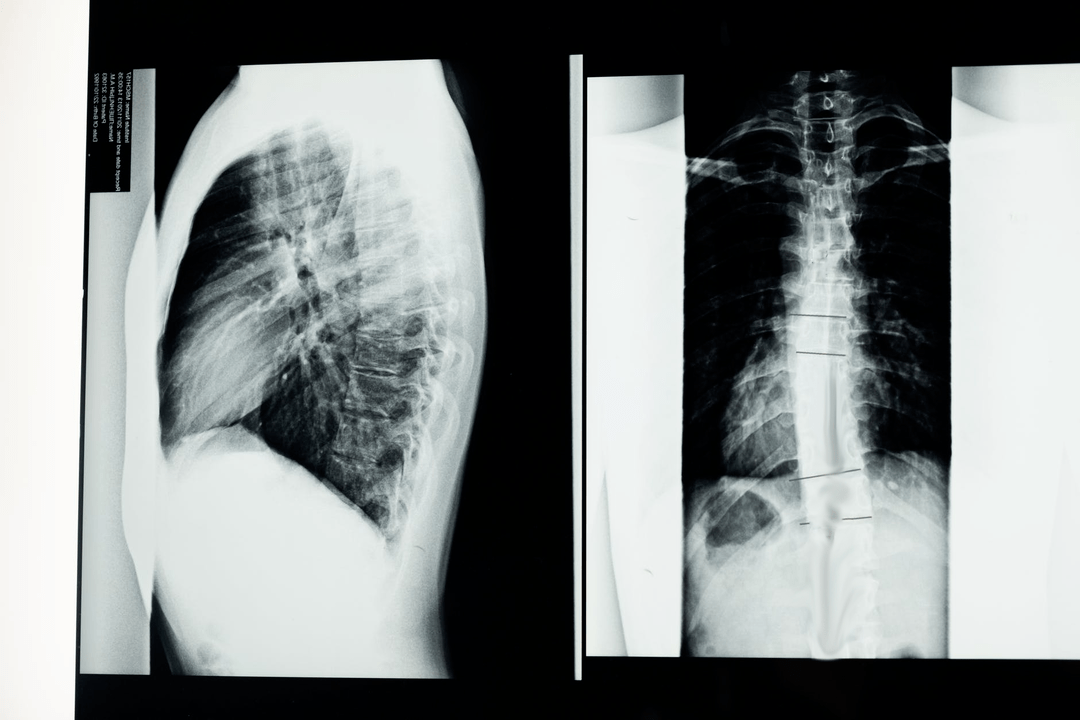

Kohdunkaulan osteokondroosin taustalla olevien syiden, merkkien ja komplikaatioiden tunnistamiseksi voidaan määrätä seuraavat tutkimukset:

- neurologiset testit;

- CT;

- kaulan röntgenkuva taivutus- ja ojennusasennossa;

- MRI.